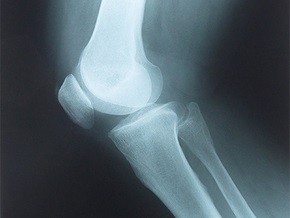

Коленный сустав образован суставными поверхностями бедренной и большеберцовой костей. Полость выстлана синовиальной оболочкой. Она вырабатывает синовиальную жидкость – своеобразную смазку, которая облегчает движения. В толще сухожилия четырехглавой мышцы бедра расположен надколенник. Сзади он прикасается к соответствующей выемке бедренной кости. Снаружи сустав имеет суставную сумку. К бугристости большеберцовой кости прикрепляются мышцы бедра. При завершении роста ростковые зоны перестают функционировать. На рентгенограмме взрослого человека вы их не найдете. При односторонней дисплазии у детей происходит отставание роста ноги. Возникает истончение мышц – мышечная атрофия бедра и голени.

При постановке диагноза учитываются жалобы ребенка, сведения о протекании беременности, о наследственности, а так же данные осмотра. Производится измерение длины ног, объем движений, оценивается состояние мышечного тонуса. Производятся МРТ, рентгенограмма в двух проекциях, УЗИ. Делается биохимическое исследование крови для определения уровня фосфора, кальция в крови.